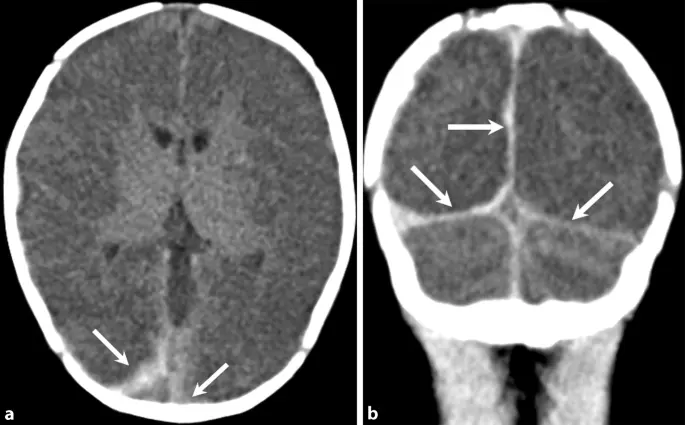

- Blutungen: Blutungen im Gehirn, zum Beispiel durch eine Hirnblutung, können zu einem Hirnödem führen.